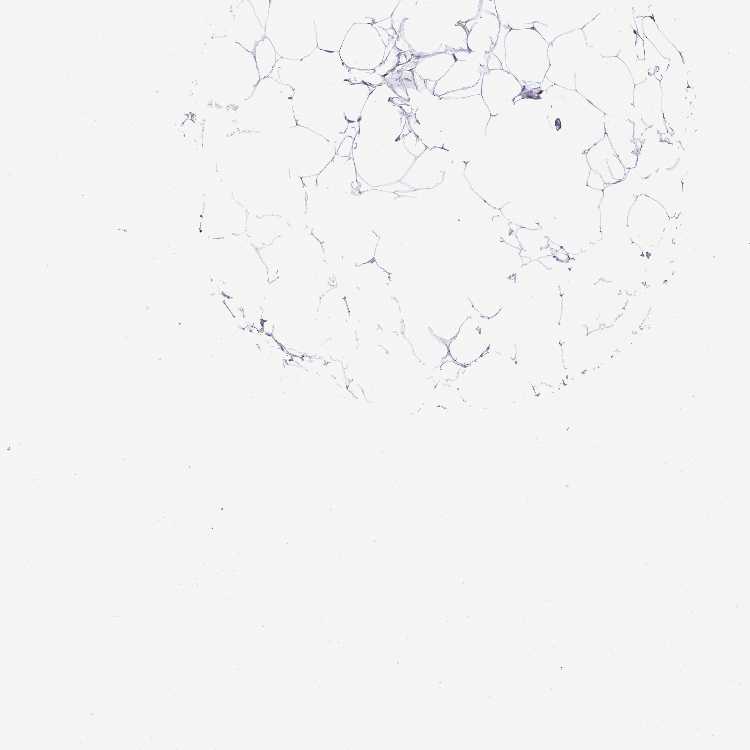

BREAST - Antibody stainingi

Antibody staining in the annotated cell types in the current human tissue is reported as not detected, low, medium, or high, based on conventional immunohistochemistry profiling in selected tissues. This score is based on the combination of the staining intensity and fraction of stained cells.

Each image is clickable and will lead to virtual microscopy that enables deeper exploration of all samples and also displays staining intensity scores, fraction scores and subcellular localization as well as patient and tissue information for each sample.

Antibody HPA046542Antibody HPA056371

Adipocytes Not detectedNot detected

Glandular cells LowMedium

Myoepithelial cells Not detectedMedium